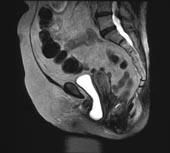

Female patients, as a result of the inherent trauma of childbirth to their pelvic floor anatomy, will commonly suffer the consequences of PFD later in life. The symptoms of PFD are cystic prolapsed ("falling urinary bladder") and its chronic cystitis symptoms of urinary frequency, burning on urination, fever, and if unaddressed, chronic kidney inflammation (pyelonephritis). The patient must be upright to see it. It commonly returns to its normal position when the patient is recumbent and therefore is not diagnosed by the patient´s physician who examines her in the recumbent position. It affects 10 million women. The UPRIGHT® MRI readily visualizes the fallen bladder when these patients are upright, so that the surgeon has full image visualization of the anatomy that has to be repaired.